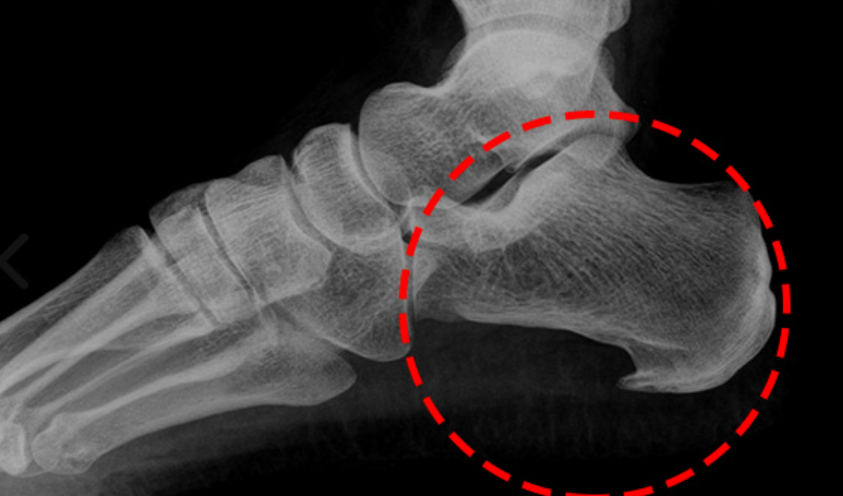

족저 근막은 종골에서 시작하여 발바닥 앞쪽으로 5개의 분지를 내어 발가락 기저부에 부착되는 강인하고 두꺼운 섬유띠입니다.

족저 근막염은 임상에서 가장 흔하게 접하게 되는 족부 병변 중 하나로, 뒤꿈치의 통증을 일으키는 질환입니다. 이 질환의 평균 발병 연령은 45세 정도입니다.

족저근막염은 발뒤꿈치와 발바닥 아치 부분에 통증을 유발하는 질환입니다.